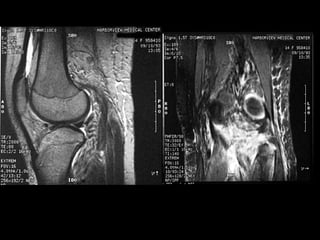

http://www.parksidemri.com/physician/casestudy/case-win03/images/case7.jpg

http://www.parksidemri.com/physician/casestudy/case-win03/fig6.html

http://www.thieme-connect.com/bilder/radu2d/200303/up004-10c

http://imaging.birjournals.org/content/vol16/issue2/images/large/IMJ52492-31.jpeg